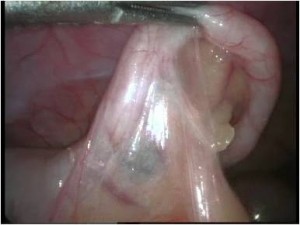

Acute Scrotum (Right scrotal Abscess)